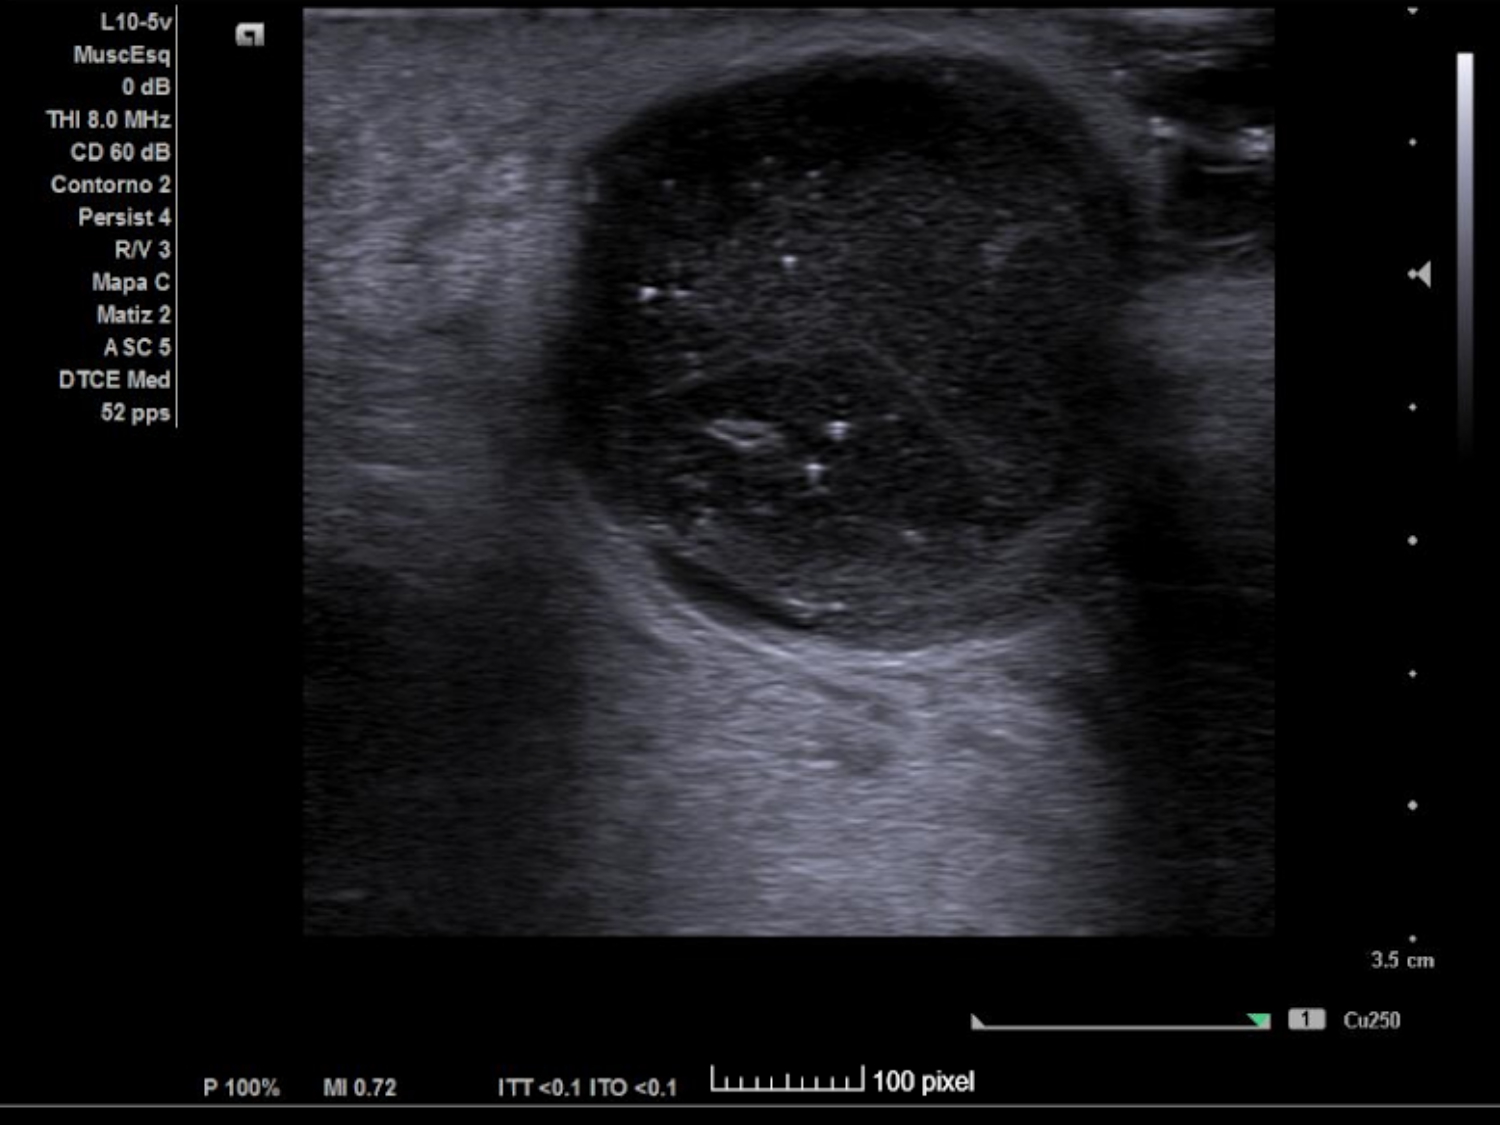

Se realiza ECO POCUS en la que se aprecia un absceso de 23 x 21 mm a menos de 1 cm de profundidad, con fácil acceso a nivel cutáneo y contenido heterogéneo, más anecoico en algunas zonas y poco tabicado.